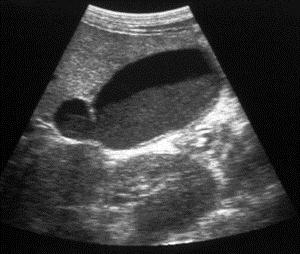

Para hacer el diagnóstico de enfermedad vesicular el estudio de elección es el Ultrasonido, y además de cálculos se pueden encontrar otras alteraciones como tabiques congénitos y lodo biliar que también provocan la inflamación de la vesícula.

ULTRASONIDO QUE DEMUESTRA UN CÁLCULO GRANDE EN LA VESICULA